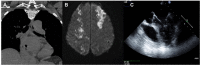

Catheter ablation of atrial ablation (AF) has become an important therapy in recent years. As with all evolving techniques, unexpected complication may occur. Atrioesophageal fistula is a very rare complication of AF catheter ablation. Described for the first time in two very experienced centers in 2004, this complication is the most dreadful and lethal among all the others related to AF catheter ablation. Its clinical presentation is extremely variable. Rapid diagnosis and surgical therapy may prevent death. This review article will summarize the risk factors, diagnosis, treatment and possible preventive strategies for this condition.